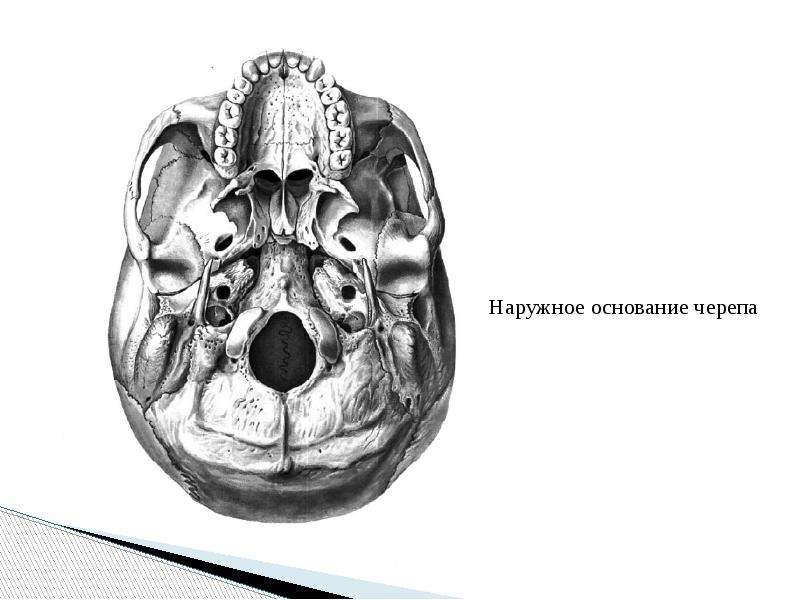

Анатомические детали: Фотографии топографии черепа с нижнего вида